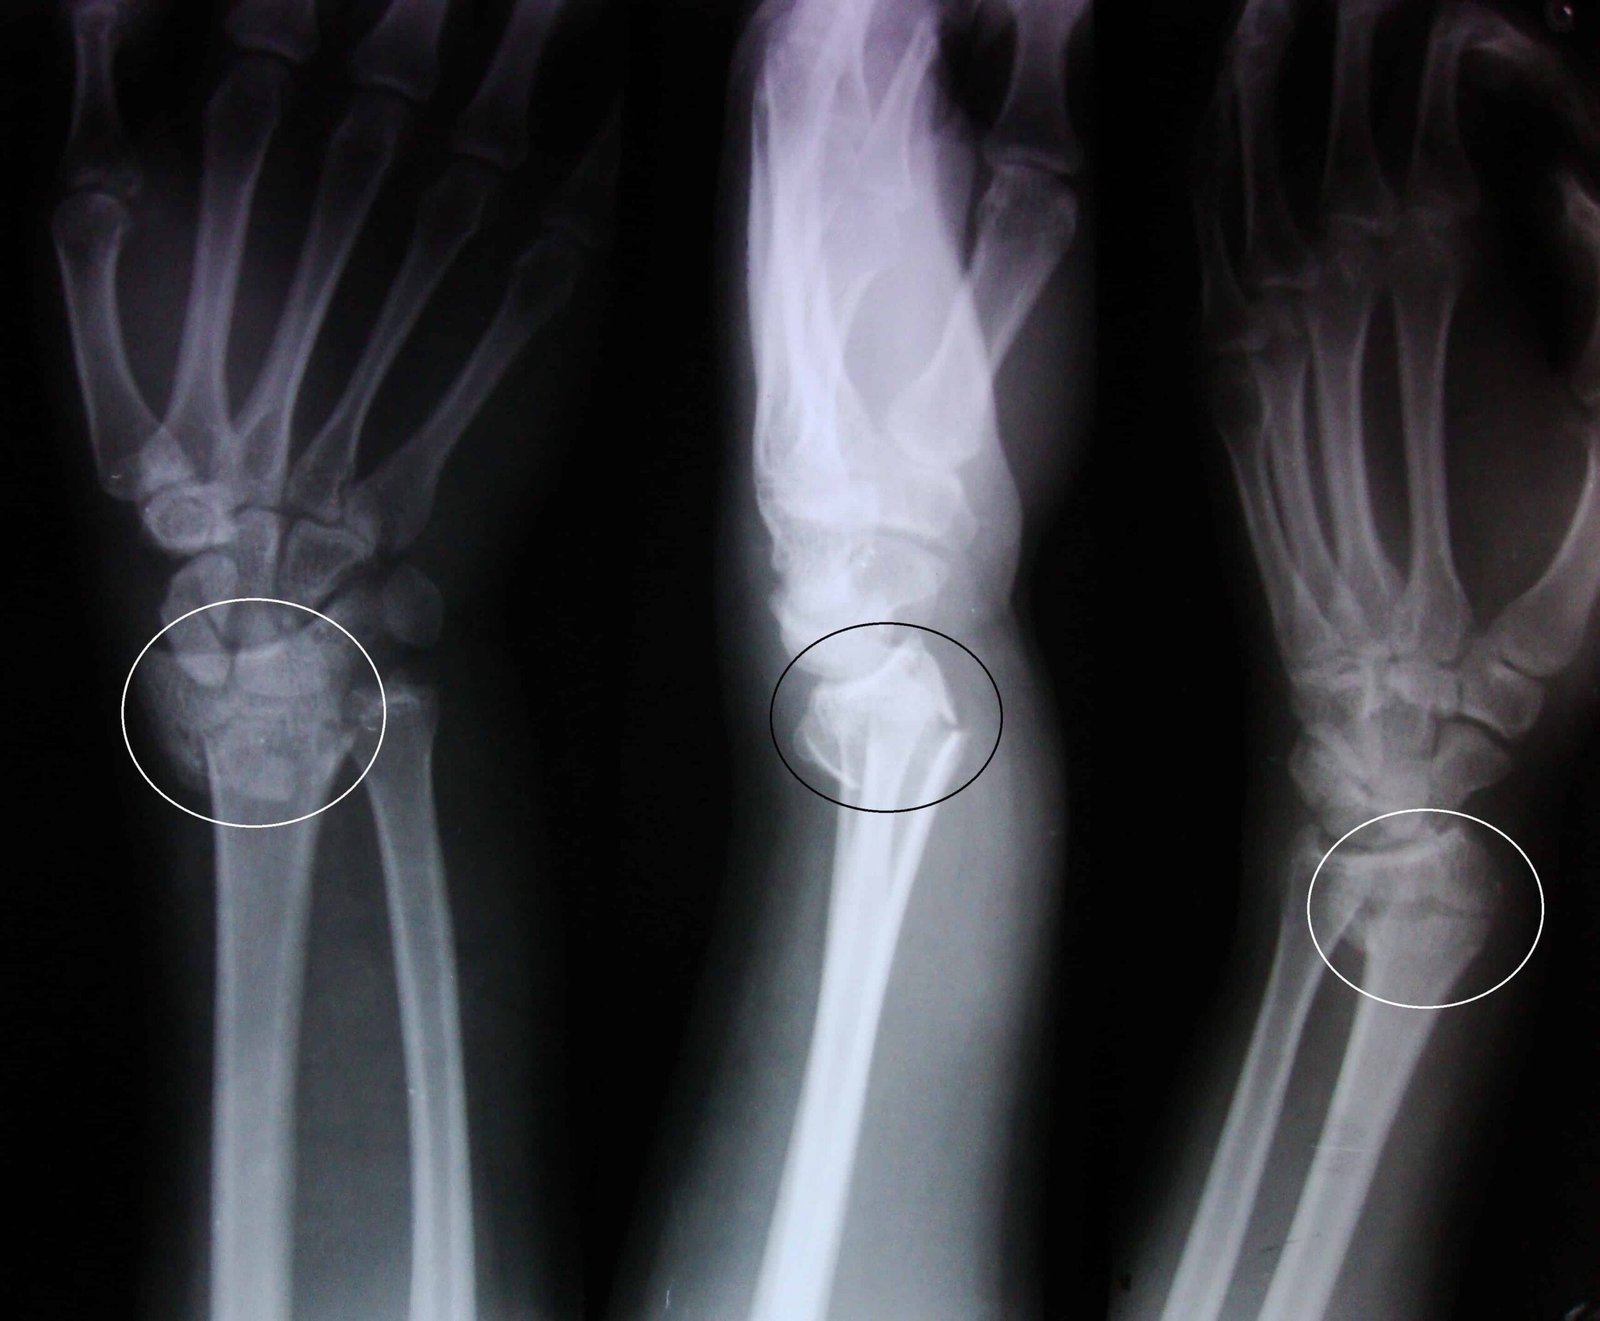

A fracture of the distal radius is known as a Smith’s fracture. The most frequent mode of injury for Smith’s fracture is a palmar fall with the wrist joint slightly dorsiflexed, though it can also be brought on by a direct impact to the dorsal forearm or by a fall with the wrist flexed. Compared to Colles’ fractures, Smith’s fractures are less frequent.

Unlike a Colles’ fracture, where the fragment is moved dorsally, a distal’ fracture fragment is displaced volarly, or ventrally. The number of fragments and whether or not the wrist joint’s articular surface is involved will depend on how hard the impact was made.

Smith fracture:

Fracture of the lower end of the radius with anterior dislocation.